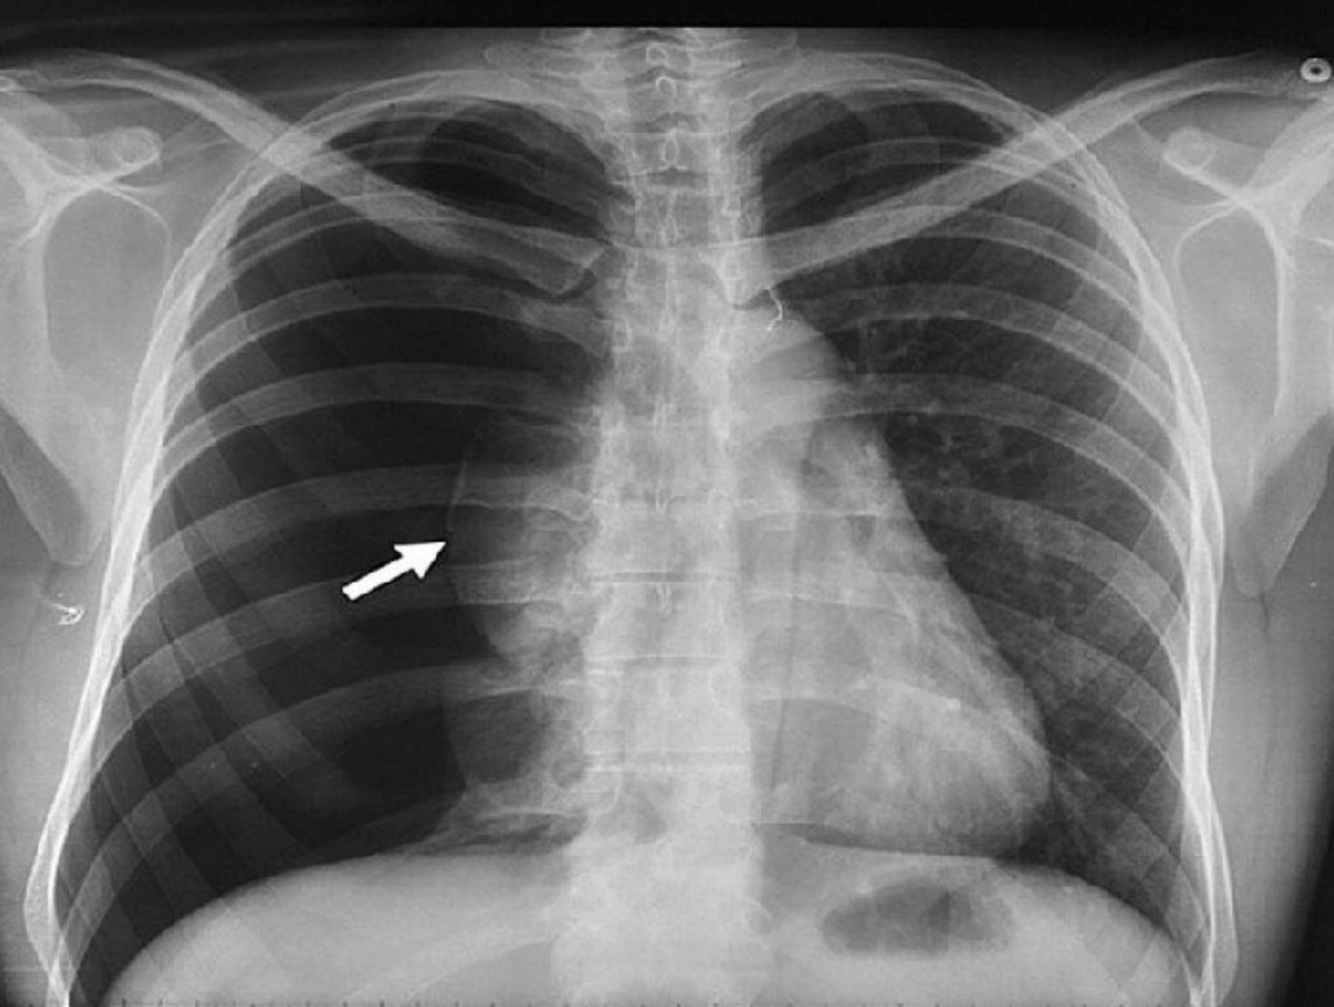

23

Q

A

sx de condensacion